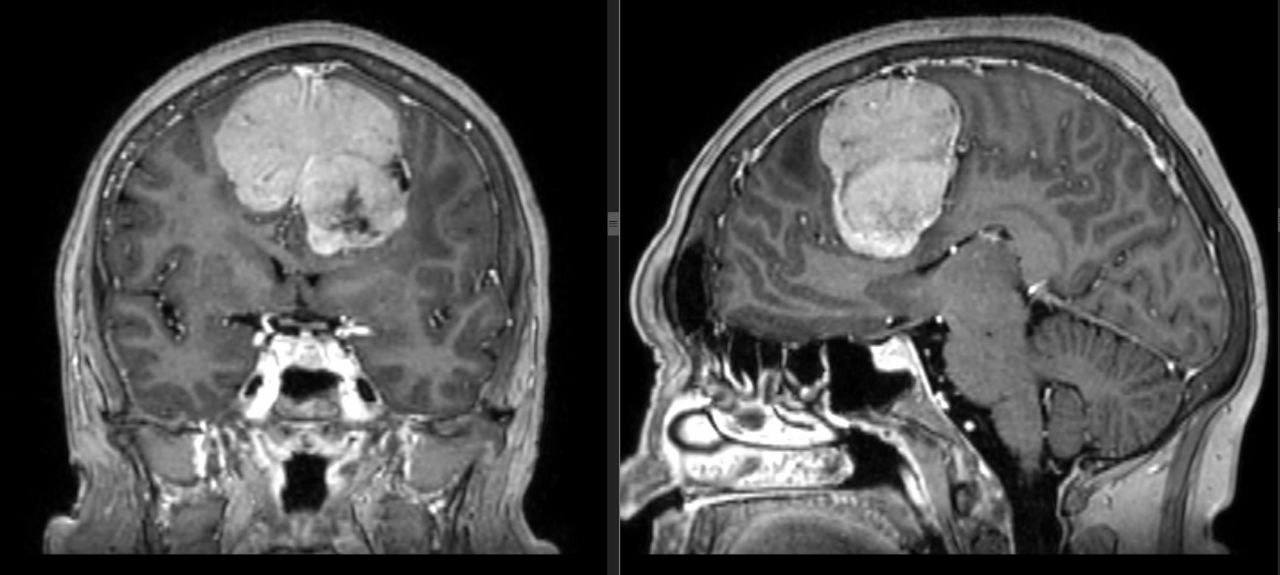

«Тревогу забили ее коллеги, когда женщина стала ошибаться в документах и перестала справляться со своими рабочими обязанностями, изменился характер, она перестала ухаживать за собой. Родственники отправили ее на обследование, где была выявлена опухоль мозга — менингиома больших размеров», — рассказала нейрохирург Ольга Мурашова.

Пациентке требовалась операция, которую выполнили Ижевские специалисты. Опухоль была полностью удалена. Сложности, возникшие в ходе операции, были связаны с гигантским размером опухоли. Новообразование занимало практически 14% объема полости черепа, его объем составил 189 кубических сантиметров. Операция продлилась 5 часов.